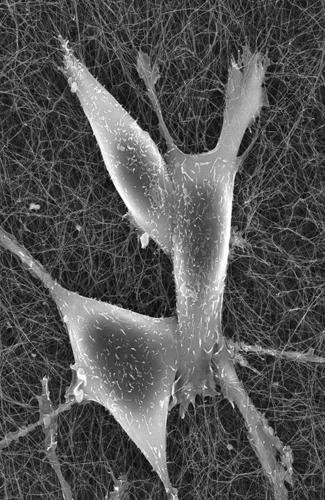

Andrew Paek’s lab uses time-lapse microscopy to create movies of cancer cells responding to chemotherapy treatment.

By following the chemotherapy response in single cancer cells that grow and divide over several days, researchers have found how key proteins in cells “decide” whether the cell will live or die.